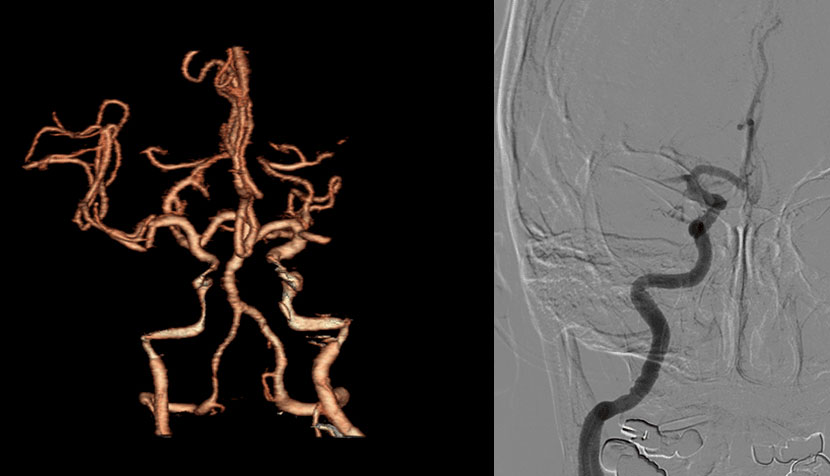

CT 혈관조영술상 뇌동맥류 발견

뇌혈관조영술로 동맥류에 대해 정밀검사